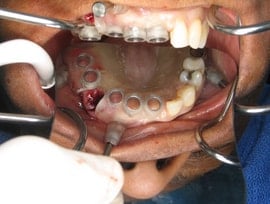

This patient had dentures that covered the palate and was very uncomfortable, and had been wearing them for years. Even though the teeth had been missing for some time, there was still adequate bone to accept implants. A Computer-guided surgical stent was fabricated, with precise guides for the implant placement. The patient’s remaining teeth were extracted, and the extraction sites were preserved with a bone graft. Then, the implants were placed according to the stent, and immediate teeth were loaded. The patient left the office with a brand new smile and no more palatal coverage, allowing for easy talking and chewing.